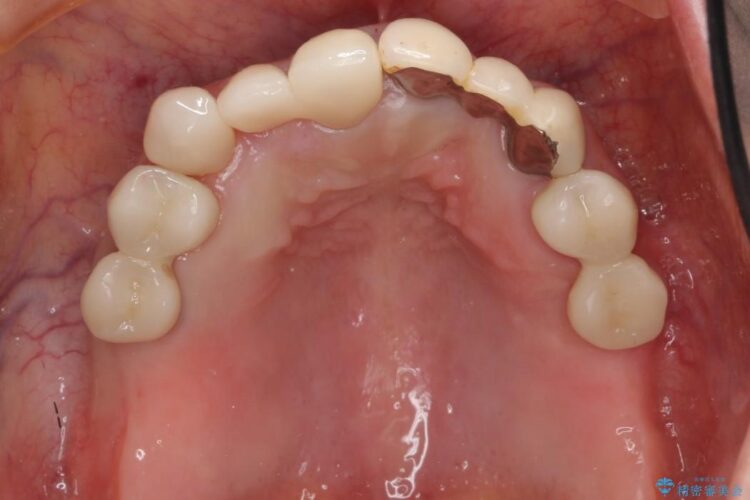

前歯のかぶせ物に関しましては、内面が金属で覆われているため歯茎にその色が透けて見えるという審美的な問題と、かぶせ物と歯の境界が不適合であるという問題がありました。

今回の症例では金属の色が透けていることを気にされていたので、土台から金属を除去し、金属を使用していないオールセラミックのかぶせ物を使用することとしました。